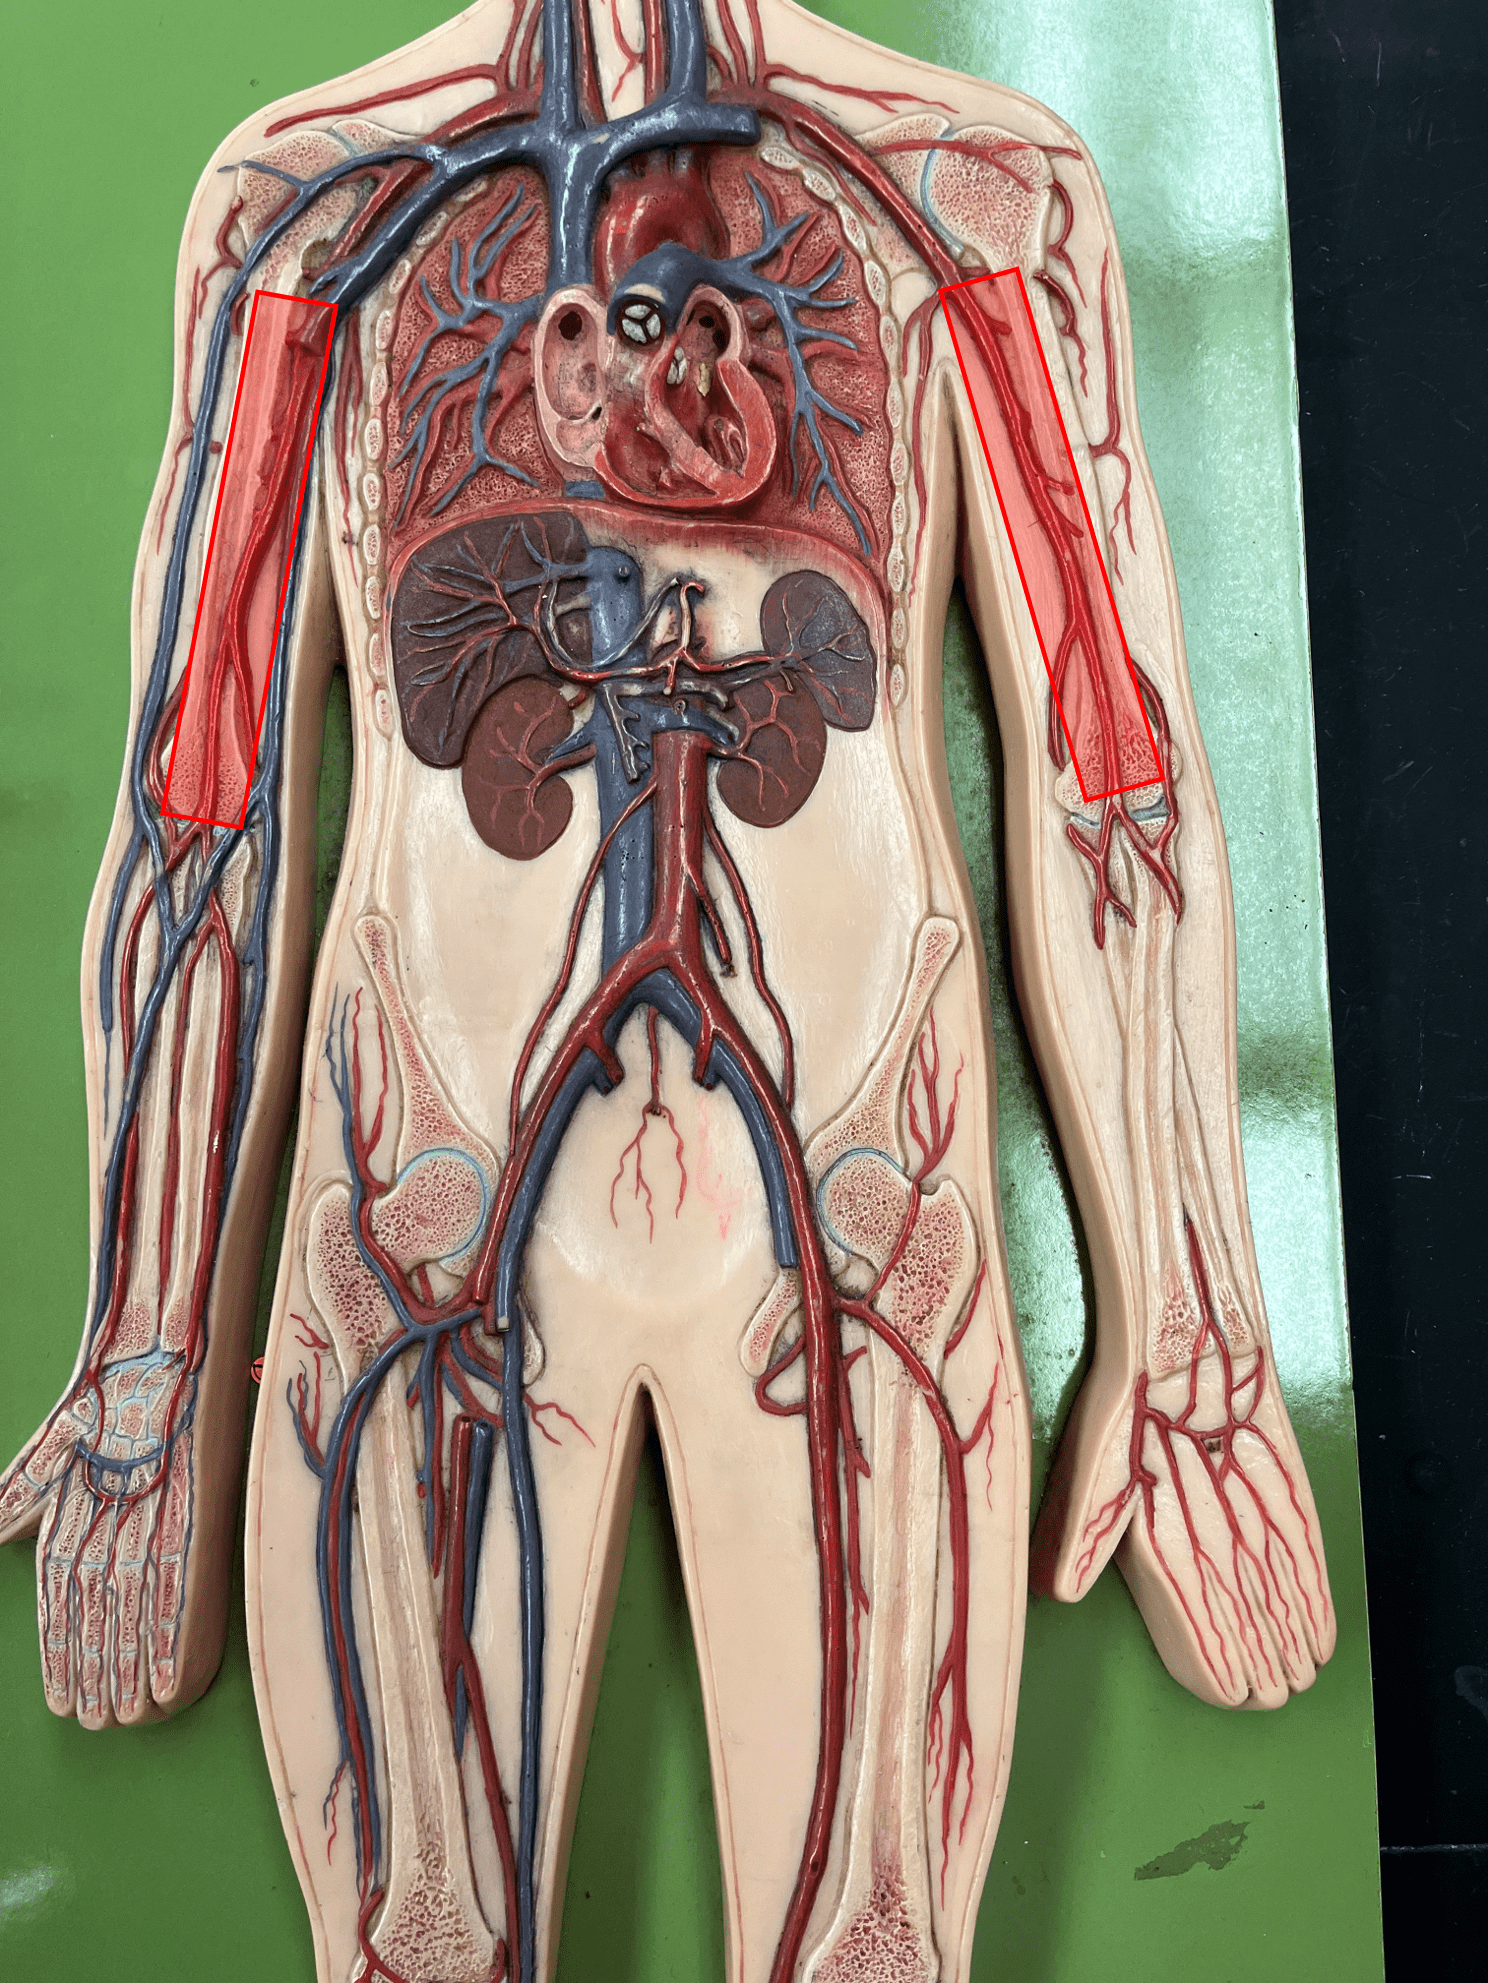

• Found between the tunica media and tunica interna.

• Allows the lumen of a blood vessel to stretch.

• Found between the tunica media and tunica interna.

• Allows the lumen of a blood vessel to stretch.

10

New cards

tunica interna

• The innermost layer of an artery.

• Consists of an inner endothelium and an outer basement membrane.

• Also known as the tunica intima.

• Consists of an inner endothelium and an outer basement membrane.

• Also known as the tunica intima.